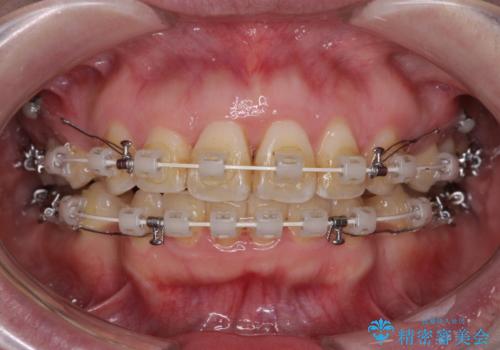

- 矯正装置

- 審美装置

上下前歯の距離が大きかったため、上下の歯が接触するまでに時間がかかりました。

それでも目安である2年半で終えることができ、患者様には大変満足していただけました。